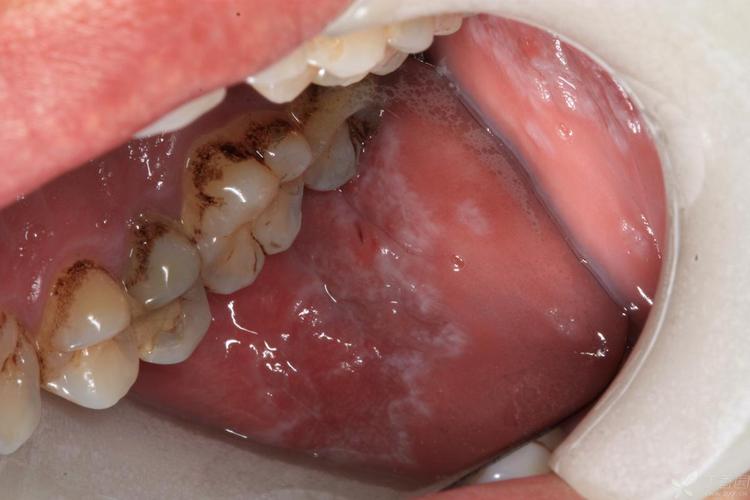

(图片来源网络,侵删)